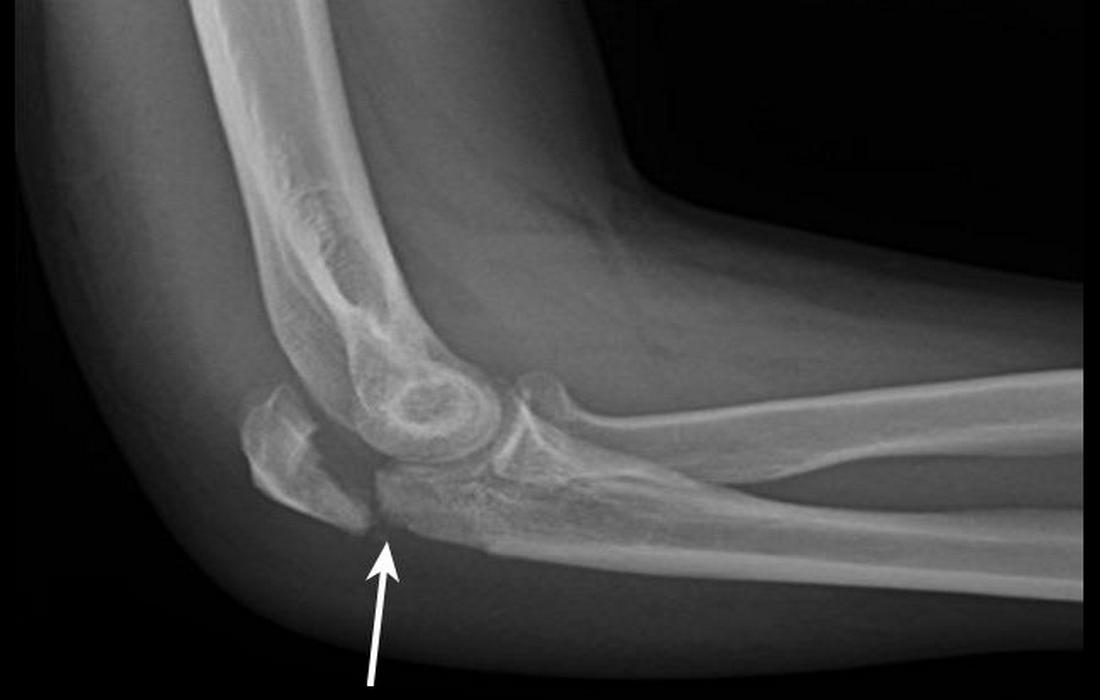

Κάταγμα Ωλεκράνου

Το ωλέκρανο είναι η “μυτερή” απόφυση που ψηλαφούμε στο πίσω μέρος του αγκώνα.

Αίτια: συχνά συμβαίνει μετά από πτώση απευθείας στον αγκώνα ή από έλξη του τρικεφάλου.

Συμπτώματα: έντονος πόνος στο πίσω μέρος, δυσκολία στην έκταση του αγκώνα, ορατή παραμόρφωση σε ορισμένες περιπτώσεις.